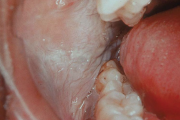

Eesmärgid – Hoolikalt suu limaskesta, keelt ja hambaid uurides otsitakse paikseid põhjusi. – Diagnoosida ravitavad süsteemsed haigused(B12-hüpovitaminoos, diabeet). – Kaebuse võimaliku põhjusena diagnoosida suukuivus (põhjuseks ravimid, nagu antikolinergikumid ja tritsüklilised Loe edasi »